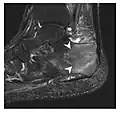

Figure 9: Proximal metaphyseal fatigue fracture of the tibia in a 27-year-old recent male military recruit. (a) Anteroposterior radiograph is within normal limits. (b) Coronal T1-weighted MR image shows a marked linear hypoattenuation along the medial tibial metaphysis (arrow) surrounded by diffuse hypointensity in keeping with posttraumatic edema.[1]

Figure 10: Calcaneal fatigue fracture in a 30-year-old male runner. Radiographs were normal (not shown). (a) Sagittal T1-weighted and (b) short tau inversion recovery images show a linear hypointensity (arrows) of calcaneal tuberosity within diffuse bone marrow edema, which appears as an ill-defined area of hyperintensity on a fluid sensitive pulse sequence (arrowheads).[1]